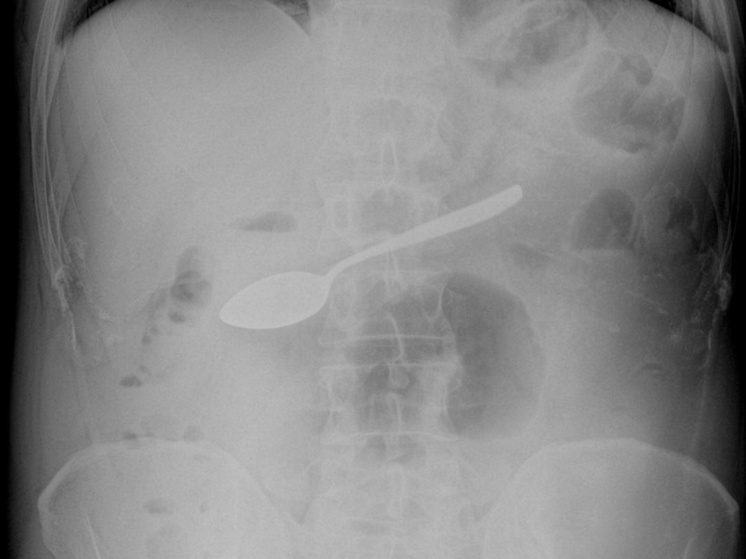

Десертную ложку достали из желудка мужчины подмосковные эндоскописты. Пациент признался, что случайно проглотил столовый прибор во время застолья. Как стало известно «МК», на днях в Мытищинскую больницу привезли 42-летнего мужчину. Его беспокоили тошнота, рвота и повышенное слюноотделение. Симптомы вызвала…. проглоченная маленькая ложка. Досадное происшествие случилось во время застолья. Пациент попытался вызвать рвоту в надежде, что ложка выйдет обратно, но это не помогло. Мало того, из пищевода ложка опустилась ниже, в желудок. Рентген подтвердил, что предмет застрял в желудке. Врачи приняли решение вытащить его с помощью гастроскопии. Эта операция потребовала большого мастерства специалистов: на пути движения ложки в организме встречается несколько сужений, включая переход из ротоглотки в пищевод. Врачам удалось успешно извлечь прибор, не повредив внутренности мужчины. Сейчас пациент чувствует себя хорошо, его уже выписали. По словам специалистов, подобные случаи в медицинской практ

Рентген подтвердил, что предмет застрял в желудке. Врачи приняли решение вытащить его с помощью гастроскопии. Эта операция потребовала большого мастерства специалистов: на пути движения ложки в организме встречается несколько сужений, включая переход из ротоглотки в пищевод.